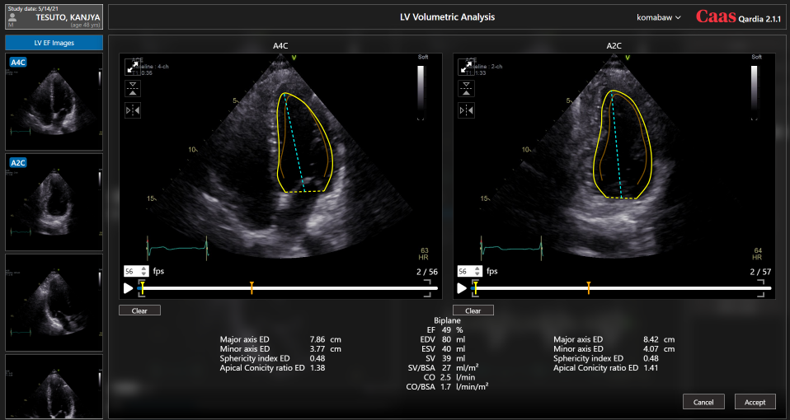

Caas Qardiaは、2D心エコー画像を定量的に評価することができるソフトウェアです。

最先端の技術を使用した自動輪郭描出機能を用いて、両心室のストレインと駆出率を自動で算出することで、グローバル及びリージョナルな心筋壁運動の最適な評価を得ることができます。